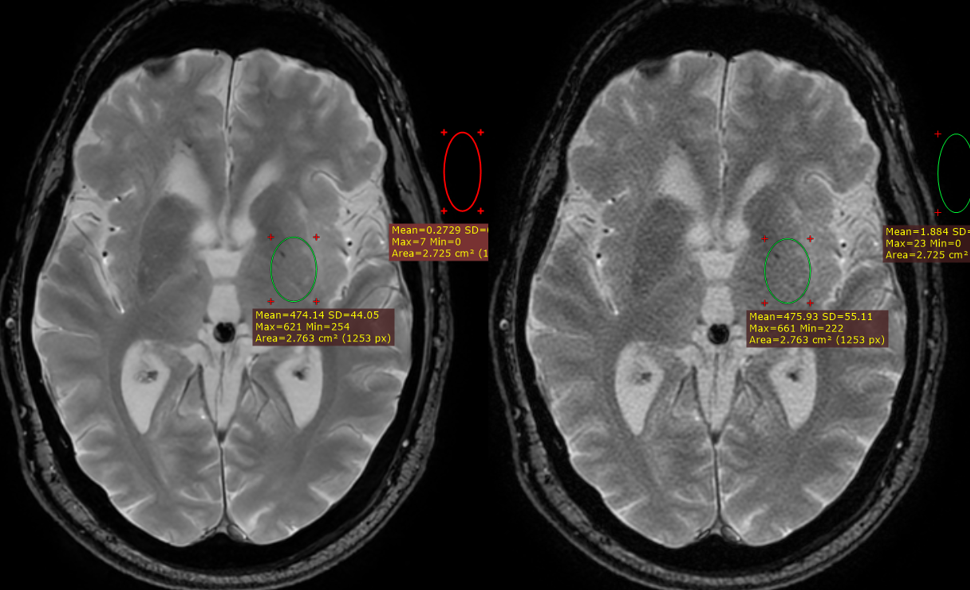

Figure 7 shows two representative images from a T2 weighted fast spin echo pulse sequence. The arrows point to areas with visible Gibbs artifacts, when the final image was reconstructed through the conventional reconstruction pipeline (right), and the arrows on the left show their DL-reconstructed counterparts, where truncation artifacts are eliminated.

Since most of the pulse sequences acquired for this study were acquired at high spatial resolution, Gibbs artifacts were not easily observed (even in the conventionally reconstructed images). However, in all images that exhibited Gibbs artifacts, the algorithm essentially eliminated them entirely, thus elevating the overall image quality.

As mentioned earlier, the algorithm was trained on pairs of k-space images of low resolution/low SNR, and high resolution/high SNR. As a result, the algorithm managed to delineate the precise pattern of the Gibbs artifacts that commonly appear in images acquired at low resolution and/or with partial filling of the k-space, thus allowing the side-benefit of Gibbs artifact elimination that we demonstrated in Figure 7.

Figure 7. 3 mm thick sagittal T2 weighted images acquired with a fast spin echo pulse sequence. SNR gains of approximately 362% were noted when the image was reconstructed through the deep learning-based reconstruction pipeline (left) compared to the conventional pipeline (right). Note the Gibbs artifact elimination (red box).